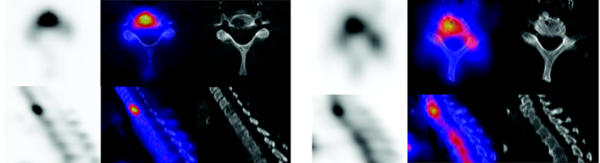

La reconnaissance de ces métastases est cruciale. Or, ces régions anatomiques sont souvent le siège de pathologies coexistantes, telles qu’une maladie dégénérative ou des fractures, qui peuvent rendre difficile le diagnostic différentiel entre pathologie bénigne ou maligne. Dans ces cas, la réalisation d’un SPECT/CT apporte une précision diagnostique améliorée en corrélant les imageries fonctionnelle et anatomique. (fig. 2)

Figure 2 - A gauche: lésion métastatique osseuse - A droite : arthrose.